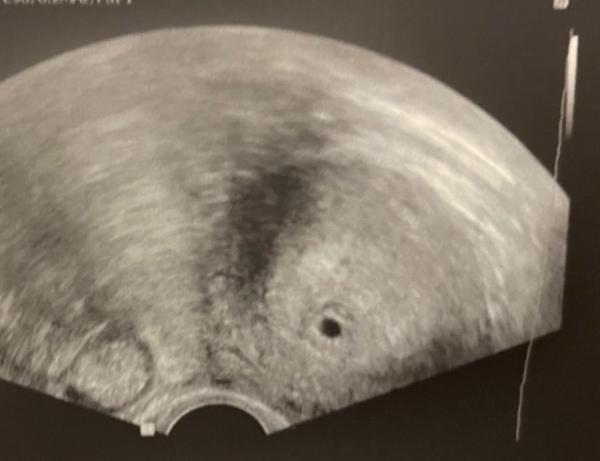

Huhu, war gestern beim FA und bin tatsächlich schwanger. Ich wollte ja auch dem positiven Test nicht ganz trauen. Bin jetzt wohl bei 5+0. Sah da das US Bild bei euch auch so aus? Ab wann konnte man in der Fruchthöhle etwas erkennen? Würde mich über Erfahrungsberichte sehr freuen. LG Kati mit Zwerg

Sieht bis jetzt ganz normal aus.

Ich zeige dir mal meins von 5+4. Da war, bei bewegen des Ultraschalls, schon eine mini kleine Anlage bzw. irgendwas drinnen zu erkennen. Eine Woche später war der Embryo mit Herzschlag da :)

das war mein Ultraschall bei 5+4